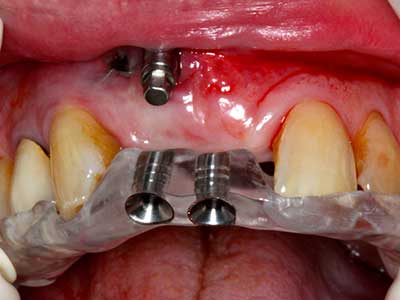

Piezo surgery has additional advantages when harvesting bone blocks. In addition to the high precision with osteotomy described above, the use of the thin saw tips specifically minimizes loss of material. Greater loss of material during harvesting can be expected with the thicker instrument tips, particularly when using Lindemann drills (Lakshmiganthan, Gokulanathan et al. 2012). The basal separation, which is necessary particularly for retromolar block transplants, is simplified by specially designed rectangular saws, with the result that piezo surgery is viewed as a precise, simple and safe procedure for harvesting retromolar bone blocks (Happe 2007) (Fig. 1-12).

Indication: Bone splitting